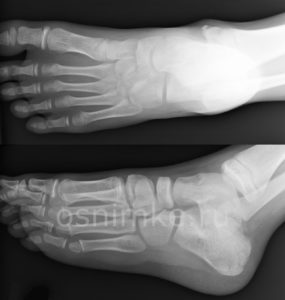

Исходя из наблюдаемой у пациента симптоматики, рентгенография стопы может проводиться в разных проекциях, с нагрузкой или без неё. Такой подход помогает провести подробную диагностику, спланировать терапевтический курс и проконтролировать результаты.

Выбор в пользу той или иной разновидности процедуры делается в зависимости от диагностируемой патологии (возрастные изменения костной ткани, врождённые недуги, артроз, механические повреждения костей и пр.).

Самый информативный диагностический метод — это рентген стопы в двух проекциях (прямой, боковой), когда снимок делают с обеспечением дополнительной нагрузки.

При съемке ступни в двух проекциях врачи получают два снимка: сбоку и сверху. Это позволяет более полно оценить состояние костей, суставов и мягких тканей стопы, выявить деформации и другие патологии.